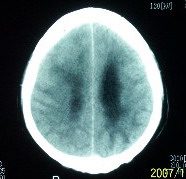

f    29岁   头闷  头晕1月余

脑膜瘤可能性大

考虑室管膜瘤可能性大,建议增强或mri

鞍上脑膜瘤

肿瘤累及颅底前颅窝,部分层面见散在钙化,中心坏死。支持:脑膜瘤!

这么大,鞍上压迫那么厉害,梗阻也比较重没有视力及其他症状吗?从肿瘤本身表现看,支持考虑颅底脑膜瘤

肿瘤长入侧脑室,侧脑室明显扩大, 病灶边界清楚,其内可见低密度坏死区,中枢神经细胞瘤?室管膜瘤?

镰旁高密度灶,中间低密度坏死区,周围水肿较轻,支持脑膜瘤诊断,建议结合增强扫描。

右额叶底部巨大等低混杂密度肿块,边界清楚,周围水肿轻度,明显占位效应。蝶鞍扩大,部分骨质破坏。

考虑脑膜瘤,建议增强扫描进一步检查。

蝶鞍受压吸收,可以排除室管膜瘤。肿瘤最大层面不在蝶鞍可以排除垂体瘤。支持脑膜瘤